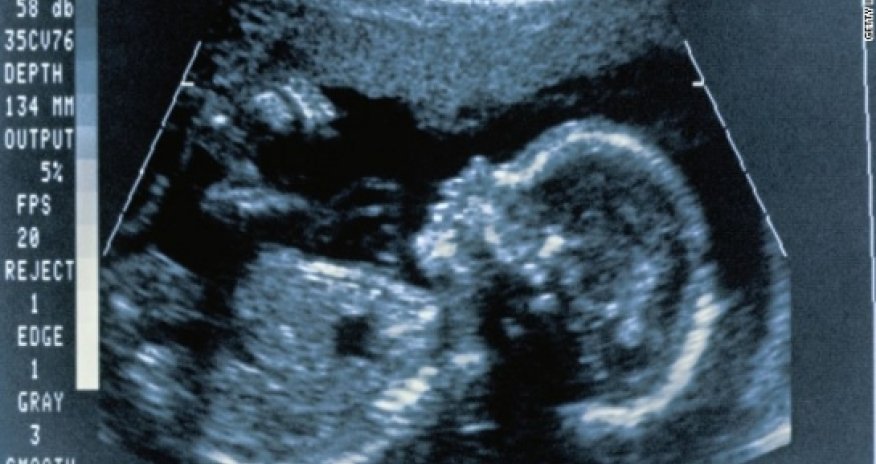

'Putting the next generation of brains in danger'

The number of chemicals known to be toxic to children's developing brains has doubled over the last seven years, researchers said.

Dr. Philip Landrigan at Mount Sinai School of Medicine in New York and Dr. Philippe Grandjean from Harvard School of Public Health in Boston, authors of the review published Friday in The Lancet Neurology journal, say the news is so troubling they are calling for a worldwide overhaul of the regulatory process in order to protect children's brains."We know from clinical information on poisoned adult patients that these chemicals can enter the brain through the blood brain barrier and cause neurological symptoms," said Grandjean."When this happens in children or during pregnancy, those chemicals are extremely toxic, because we now know that the developing brain is a uniquely vulnerable organ. Also, the effects are permanent."The two have been studying industrial chemicals for about 30 years. In 2006, they published data identifying five chemicals as neurotoxicants -- substances that impact brain development and can cause a number of neurodevelopmental disabilities including attention-deficit hyperactivity disorder, autism, dyslexia and other cognitive damage, they said.Those five are lead, methylmercury, arsenic, polychlorinated biphenyls, or PCBs, and toluene.Banned in the United States in 1979, PCBs were used in hundreds of products including paint, plastic, rubber products and dyes. Toluene is in household products like paint thinners, detergents, nail polish, spot removers and antifreeze.Now, after further review, six more chemicals have been added to the list: manganese; fluoride; tetrachloroethylene, a solvent; a class of chemicals called polybrominated diphenyl ethers, or flame retardants; and two pesticides, chlorpyrifos, which is widely used in agriculture, and dichlorodiphenyltrichloroethane, or DDT."The continuing research has identified six new chemicals that are toxic to the developing human brain," said Landrigan. "We're turning up chemicals at the rate of about one a year that we're discovering are capable of damaging the developing brain of a human fetus or human infant."To examine fluoride, which is in tap water in many areas, Landrigan and Grandjean looked at an analysis of 27 studies of children, mostly in China, who were exposed to fluoride in drinking water at high concentrations. The data, they said, suggests a decline on average of about seven IQ points.There's another big concern: "We are very worried that there are a number of other chemicals out there in consumer products that we all contact every day that have the potential to damage the developing brain, but have never been safety tested," Landrigan said."Over the last six or seven years we are actually adding brain toxic chemicals at a greater speed than we are adding toxicity evidence in children's brains," Grandjean said."At least 1,000 chemicals using lab animals have shown that they somehow interfere with brain function in rodents -- rats and mice -- and those are prime candidates for regulatory control to protect human developing brains. But this testing has not been done systematically."At greatest risk? Pregnant women and small children, according to Grandjean. According to the review, the biggest window of vulnerability occurs in utero, during infancy and early childhood.The impact is not limited to loss of IQ points."Beyond IQ, we're talking about behavior problems -- shortening of attention span, increased risk of ADHD," Landrigan said."We're talking about emotion problems, less impulse control, (being) more likely to make bad decisions, get into trouble, be dyslexic and drop out of school. ... These are problems that are established early, but travel through childhood, adolescence, even into adult life."BPA, phthalate exposure may cause fertility problemsIt's not just children: All these compounds are toxic to adults, too. In fact, in 2006 the pair documented 201 chemicals toxic to the adult nervous system, usually stemming from occupational exposures, poisonings and suicide attempts.The American Chemistry Council, meanwhile, called the review a "rehash" of the authors' first review."This iteration is as highly flawed as the first, as once again the authors ignore the fundamental scientific principles of exposure and potency," said council spokesman Scott Jensen."What is most concerning is that the authors focus largely on chemicals and heavy metals that are well understood to be inappropriate for children's exposure, are highly regulated and/or are restricted or being phased out. They then extrapolate that similar conclusions should be applied to chemicals that are more widely used in consumer products without evidence to support their claims. Such assertions do nothing to advance true scientific understanding and only create confusion and alarm."Landrigan and Grandjean now say all untested chemicals in use and all new chemicals should be tested for developmental neurotoxicity.This is not a new concept. In 2007, the European Union adopted regulations known as REACH -- Registration, Evaluation, Authorisation and Restriction of Chemicals -- to protect human health from risks posed by chemicals. REACH covers all chemicals, placing the burden of proof on companies to prove that any chemicals they make are safe."We are behind right now and we're falling further behind," Landrigan said. "... I find it very irritating some of the multinational manufacturers are now marketing products in Europe and the U.S. with the same brand name and same label, but in Europe (they) are free of toxic chemicals and in the U.S. they contain toxic chemicals."The best example of this, he said, is cosmetics and phthalates. Phthalates are a group of chemicals used in hundreds of products from cosmetics, perfume, hair spray, soap and shampoos to plastic and vinyl toys, shower curtains, miniblinds, food containers and plastic wrap.You can also find them in plastic plumbing pipes, medical tubing and fluid bags, vinyl flooring and other building materials. They are used to soften and increase the flexibility of plastic and vinyl.In Europe, cosmetics don't contain phthalates, but here in the United States some do.Phthalates previously were used in pacifiers, soft rattles and teethers. But in 1999, after a push from the U.S. Consumer Product Safety Commission, American companies stopped using them in those products."We certainly have the capability, it's a matter of political will," Landrigan said. "We have tried in this country over the last decade to pass chemical safety legislation but the chemical industry and their supporters have successfully beat back the effort."However, the Food and Drug Administration said two of the most common phthalates, -- dibutylphthalate, or DBP, used as a plasticizer in products such as nail polishes to reduce cracking by making them less brittle, and dimethylphthalate, or DMP used in hairsprays -- are now rarely used in this country.Diethylphthalate, or DEP, used in fragrances, is the only phthalate still used in cosmetics, the FDA said."It's not clear what effect, if any, phthalates have on human health," according to the FDA's website. "An expert panel convened from 1998 to 2000 by the National Toxicology Program (NTP), part of the National Institute for Environmental Safety and Health, concluded that reproductive risks from exposure to phthalates were minimal to negligible in most cases."But Grandjean is unfazed."We know enough about this to say we need to put a special emphasis on protecting developing brains. We are not just talking about single chemicals anymore. We are talking about chemicals in general.""This does not necessarily mean restrict the use of all chemicals, but it means that they need to be tested whether they are toxic to brain cells or not," he said."We have the test methods and protocols to determine if chemicals are toxic to brain cells. If we look at this globally, we are looking at more than a generation of children -- a very high proportion of today's children have been exposed to lead, mercury and other substances, including substances that have not yet been tested but are suspect of being toxic to brain development."The Environmental Working Group is an environmental health research organization that specializes in toxic chemical analysis and has long called for reforms. In 2004, the group tested 10 samples of umbilical cord blood for hundreds of industrial pollutants and found an average of 200 in each sample."Here in the U.S., the federal law put in place to ostensibly protect adults and children from exposures to dangerous chemicals, including those that can present serious risks to the brain and nervous systems, has been an abject failure," said Environmental Working Group spokesman Alex Formuzis."The 1976 Toxic Substances Control Act has instead been largely responsible for the pollution in people beginning in the womb, where hundreds of industrial contaminants literally bathe the developing fetus."Landrigan is recruiting pregnant women for a new study that will test for chemical exposures. He said it's inevitable that over the next few years more chemicals will be added to the list.His concern? "The ability to detect these chemicals lags behind the chemical industries' ability to develop new chemicals and put them into consumer products. That's why we need new legislation in this country to close that gap.""We are lagging behind," Grandjean said. "And we are putting the next generation of brains in danger."(CNN)ANN.Az